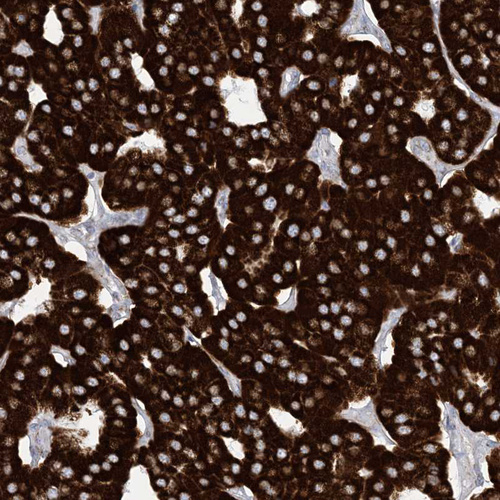

Immunohistochemistry analysis in human kidney and pancreas tissues using HPA034537 antibody. Corresponding SAMM50 RNA-seq data are presented for the same tissues.